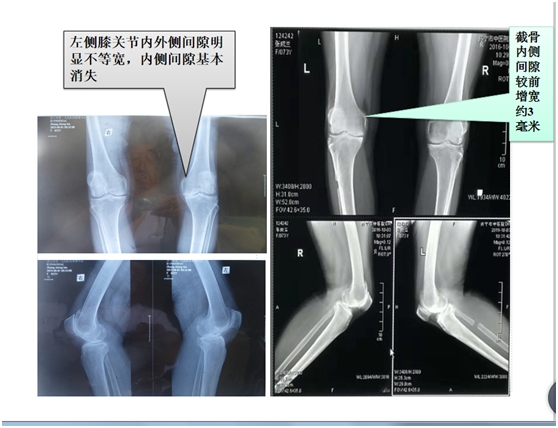

经科室讨论,申报医院新项目。经过详细的术前检查及与患者沟通交流,在硬膜外麻下行左腓骨上段截骨均衡(减压)+右膝臭氧靶向介入+激光清理术;5天后又在局麻下行右膝臭氧靶向介入+激光清理术。12天后在局麻下行双膝臭氧靶向介入+激光清理术+双膝针刀松解术。术后膝关节疼痛症状减轻,左侧腓骨截骨后3天弃拐棍小慢步行,双下肢功能逐渐恢复,双膝关节摄片(见图片一DR片显示膝关节内侧间隙增宽)。住医院16天出院时: 诉双膝关节部疼痛消失,右膝缓解明显,双下肢步行活动较前改善,左小腿前侧至足背部感觉麻木部分好转。出院后密切随访,膝关节无疼痛,生活自理,安享晚年。

图片一: DR 片膝关节退行性变内翻畸形,截骨前后关节间隙宽窄对比